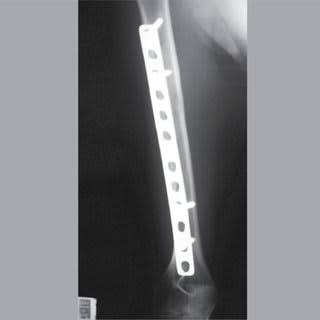

Exames no Instituto Médico Legal (IML) apontaram que a vítima usava uma haste metálica no fêmur

Foto: Richard Nunes /Rondoniaovivo